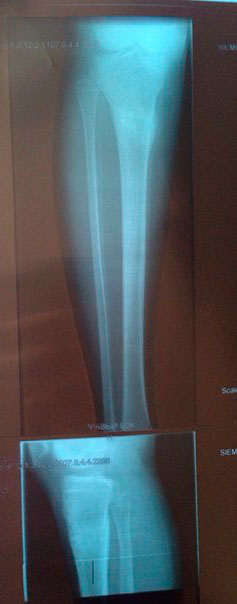

Рентген контроль в 81 день с момента снятия аппаратов.

Сращение железное, никаких ограничений! На физ-ру ходить можно! И ждём фото ножек девочки!